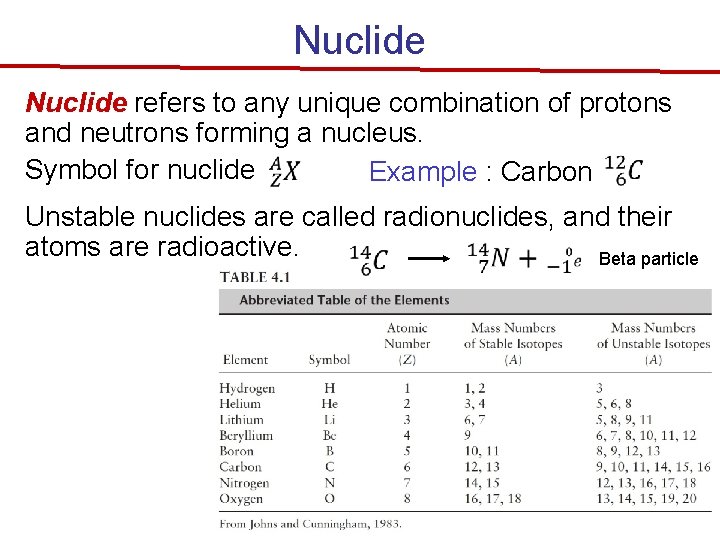

Nuclide refers to any unique combination of protons and neutrons forming a nucleus. Symbol for nuclide Example : Carbon Unstable nuclides are called radionuclides, and their atoms are radioactive. Beta particle